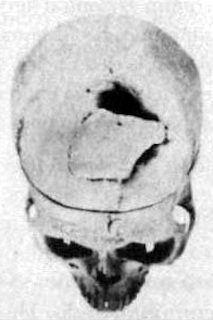

Cuando murió Gage, en 1861, no se le practicó una autopsia. Debido a la confusión que hubo durante la guerra civil, las noticias no viajaban bien, y Harlow se enteró del fallecimiento sólo cinco años más tarde. Es indudable que le afectó la desaparición de Gage, pero además debió sentirse muy abatido por haber perdido la oportunidad de estudiar el cerebro del difunto. Tan abatido en verdad, que escribió a la hermana de Gage para hacerle una solicitud algo estrafalaria. Le rogó que exhumara el cadáver para recuperar la calavera, y poder guardarla como prueba del caso.Nuevamente correspondió a Phineas Gage ser el protagonista de una escena dantesca. Su hermana, con su marido D. D. Shattuck —junto con un cierto Dr. Coon (entonces alcalde de San Francisco) y el médico de la familia— presenciaron cómo un funcionario de la funeraria destapaba el ataúd y extraía la calavera de Gage. La estaca, colocada junto al cadáver, también fue recuperada y todo ello enviado a Harlow, en el este. Cabeza y hierro siguen desde entonces en el Warren Medical Museum de la Facultad de Medicina de Harvard, en Boston.

Los dos objetos permitieron que Harlow probara que el caso era real y no un invento, y que había existido un individuo con esa lesión. Ciento veinte años después, la calavera sirvió de trampolín a Hanna Damasio para una labor detectivesca que completó el fragmentario trabajo de Harlow y sirvió de puente entre Gage y la investigación moderna de la función del lóbulo frontal.

Primero, trató de determinar con exactitud la trayectoria de la estaca. Ingresando al cráneo a través de la mejilla izquierda, debajo del pómulo, el hierro rompió la parte posterior de la cavidad orbital (la cuenca del ojo), situada inmediatamente encima. Siguiendo su trayectoria ascensional, debe haber penetrado en la parte frontal del cerebro, cerca de la línea medial, aunque es difícil determinar exactamente dónde. La trayectoria diagonal hace pensar que impactó primero el lado izquierdo y después parte del derecho. El punto inicial de choque fue probablemente la región orbital frontal, directamente encima de las cavidades orbitales. A su paso, la barra habría destrozado parte de la superficie interna del lóbulo frontal izquierdo y quizá del derecho; finalmente, al salir, habría dañado parte de la zona posterior —o dorsal— del lóbulo frontal, sin duda en el lado izquierdo, acaso también en el derecho.

Puesto que a Phineas Gage no se le podía practicar una tomografía computarizada, Hanna Damasio ideó un acercamiento indirecto a su cerebro[21]. Obtuvo la cooperación de Albert Galaburda, neurólogo de la Facultad de Medicina de Harvard, que fue al Warren Medical Museum y fotografió cuidosamente la caja craneana de Gage desde diversos ángulos y midió la distancia entre las zonas óseas deterioradas y una diversidad de hitos óseos estándar.

El análisis de dichas fotografías (junto con las descripciones de la herida) ayudó a estrechar la latitud de los posibles itinerarios de la barra de hierro. Permitió asimismo que Hanna Damasio y su colega, el neurólogo Thomas Grabowski, recrearan el cráneo de Gage en coordenadas tridimensionales y dedujeran de ellas las coordenadas cerebrales más adecuadas a su tipo de caja ósea. Con la ayuda de su colaborador, el ingeniero Randall Frank, Damasio diseñó un símil en una computadora de alto poder. Reconstruyeron así una barra tridimensional con las dimensiones precisas del hierro que atravesó el cráneo de Gage, y lo situaron en el ahora escaso rango de trayectorias posibles. Los resultados se pueden ver en las figuras 2-7 y 2-8.

Figura 2-7. Fotografía del cráneo de Gage, obtenida en 1992.